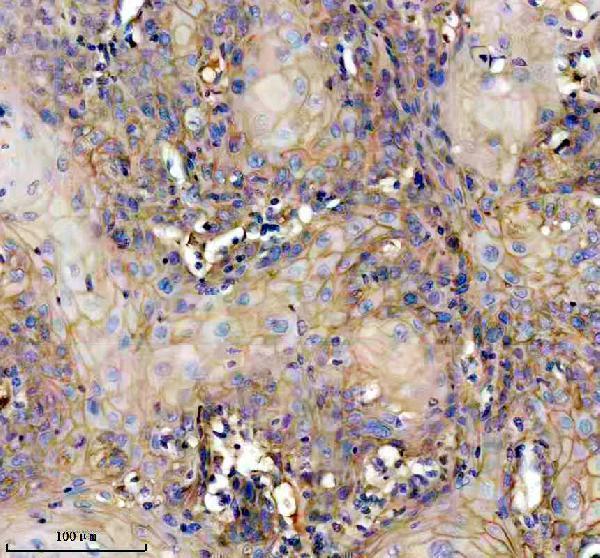

Expressed in the suprabasal region of the epidermis, in hair follicles, the basement membrane at the dermo- epidermal junction (occasionally extending into the basement membrane of dermal blood vessels), wounded skin and several invasive squamous cell carcinomas (at protein level). Expressed in normal and wounded skin and various squamous cell carcinomas.

Secreted, extracellular space. Cell membrane; Peripheral membrane protein. Extracellular and plasma membrane-associated. Colocalizes with HSPG2 in the pericellular environment of squamous cell carcinomas.